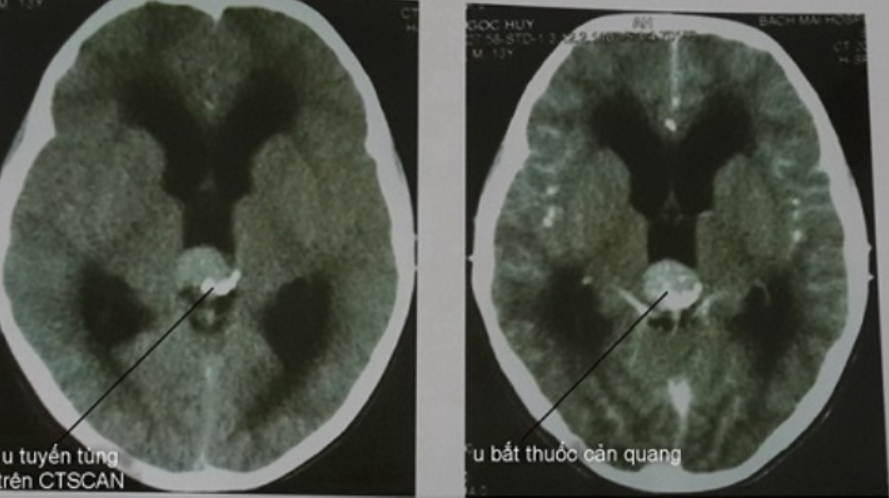

Những khảo sát hình ảnh học của u tuyến tùng có vai trò rất quan trọng nhất là chụp cắt lớp điện toán (CT-Scan) và chụp cộng hưởng từ (MRI)

- Hình ảnh trên CT-Scan rất có giá trị trong chẩn đoán khối u tuyến tùng. Khối u vùng này thường có vôi hóa trong khối u và ngấm thuốc cản quang mạnh, đồng thời chèn ép gây tắc nghẽn và làm dãn não thất.